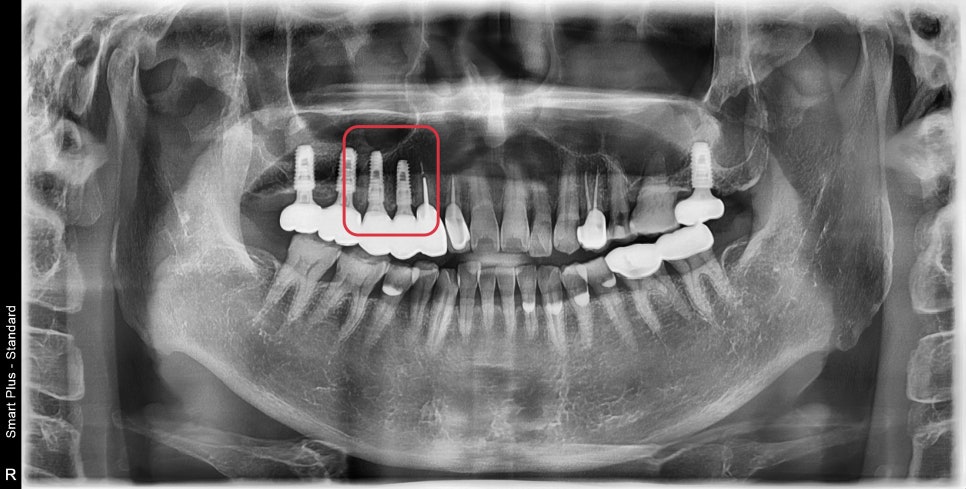

사진에 표시된 부분이 과거에 신경치료가 되어있었고

주변으로 염증이 생겨 치아를 지지해 주는 뼈가 흡수되어

치아 동요도가 관찰되었습니다.

화살표로 표시된 부분이 염증으로 인해 흡수되어

임플란트를 식립하더라도 주변 뼈가 없어

노출이 될 수밖에 없는 상태였습니다.

역시 초진 3D CT에서 치아를 감싸는 한쪽 벽을 이루는 뼈가 흡수되어

치아 뿌리가 노출된 상태에서 이 역시 발치 후 즉시 임플란트 식립 시

기존 잇몸을 차폐막으로 이용하여 치조골 이식술을 동반했습니다.